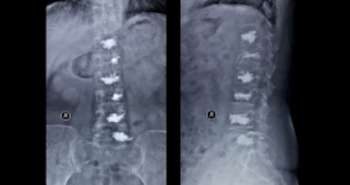

A total of fifty healthy inactive women were randomized to control group (CG), low impact group (LIG) and high impact group (HIG). Participants of CG hired from Toledo and HIG/LIG from Madrid. A 12-week intervention program of Aquagym and Zumba (three 40 sessions per week) was completed by both LIG and HIG. The areal bone mineral density (aBMD) and bone mineral content (BMC) at total body less head (TBLH), right hip and lumbar spine and were measured using the dual-energy X-ray absorptiometry (DXA).

There were no significant difference observed in the BMC and aBMD between LIG and HIG. However, HIG and CG showed substantial differences in intertrochanter aBMD, hip aBMD, and femoral neck aBMD. The  LIG and CG showed significant differences in femoral neck aBMD. These findings indicate Zumba and Aquagym is a great approach to reduce deterioration of bone mass.